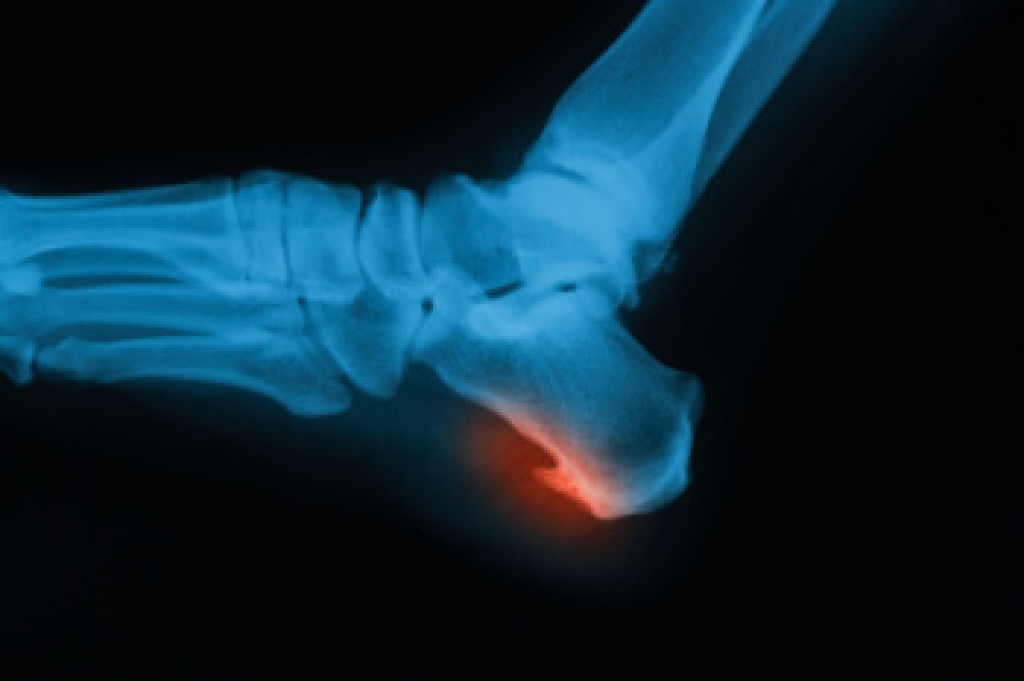

What Is Turf Toe?

Turf toe is a sprain of the ligaments surrounding the big toe joint, typically occurring in athletes who play on artificial turf, though it can affect anyone engaged in activities that involve pushing off the big toe forcefully. Turf toe is usually caused by repetitive hyperextension of the big toe, often when an athlete  or dancer pushes off the ground. The injury is classified into three grades. Grade 1 involves mild stretching of the ligaments, causing minor pain and swelling. Grade 2 includes partial tearing, leading to moderate pain, bruising, and difficulty in movement. Grade 3 is a complete tear, resulting in severe pain, significant swelling, and joint instability. Symptoms of turf toe include pain, swelling, and limited range of motion in the big toe. Diagnosis is made through a physical exam and imaging studies like X-rays. Treatment varies by grade, ranging from rest for milder cases to immobilization or surgery for severe injuries. If you are suffering with what you think might be turf toe, it is suggested that you consult a podiatrist for a proper diagnosis and treatment.